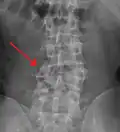

A burst fracture of L4 as seen on plane X ray -

Diagnosis is by medical imaging.